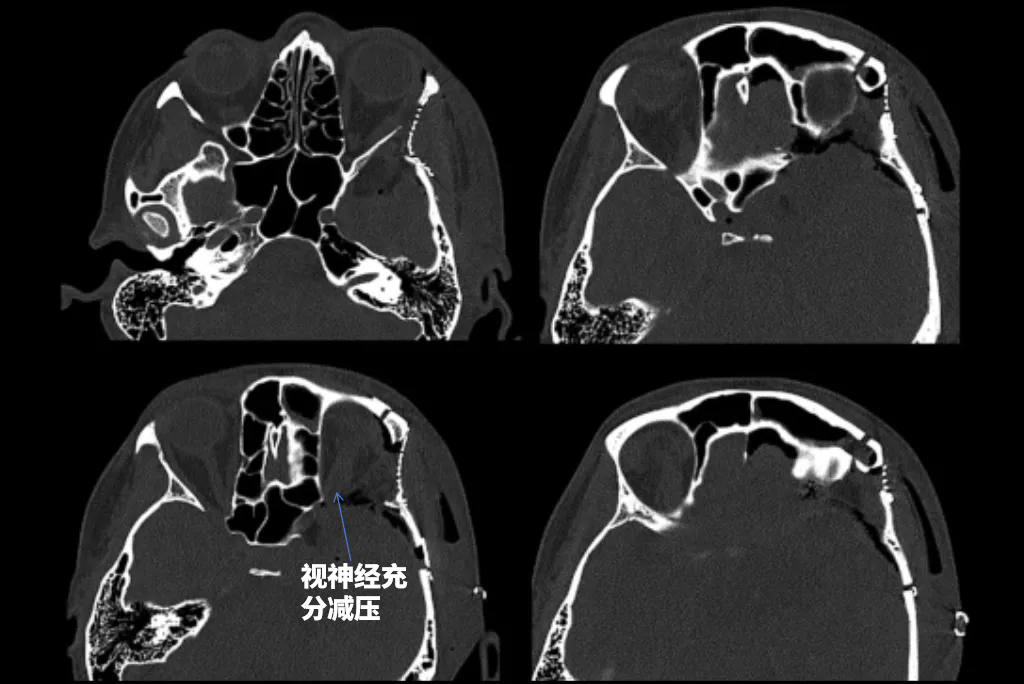

▼本例特殊之处在于骨窗CT显示前床突气化。正常情况下,前床突是实心的,前床突气化术后有脑脊液漏的风险,所以颅底修补至关重要。

▼术后CT:这些骨窗图显示了骨质磨除范围和术后重建的程度